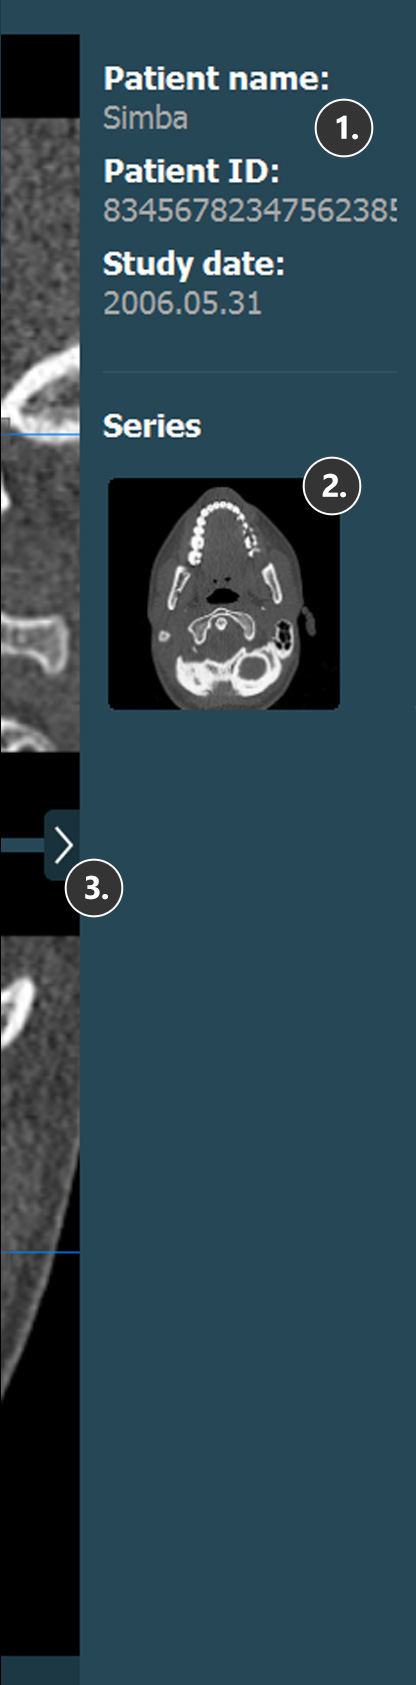

Viewer Area¶

HU (Hounsfield Unit) pixel value

Patient information

Study information